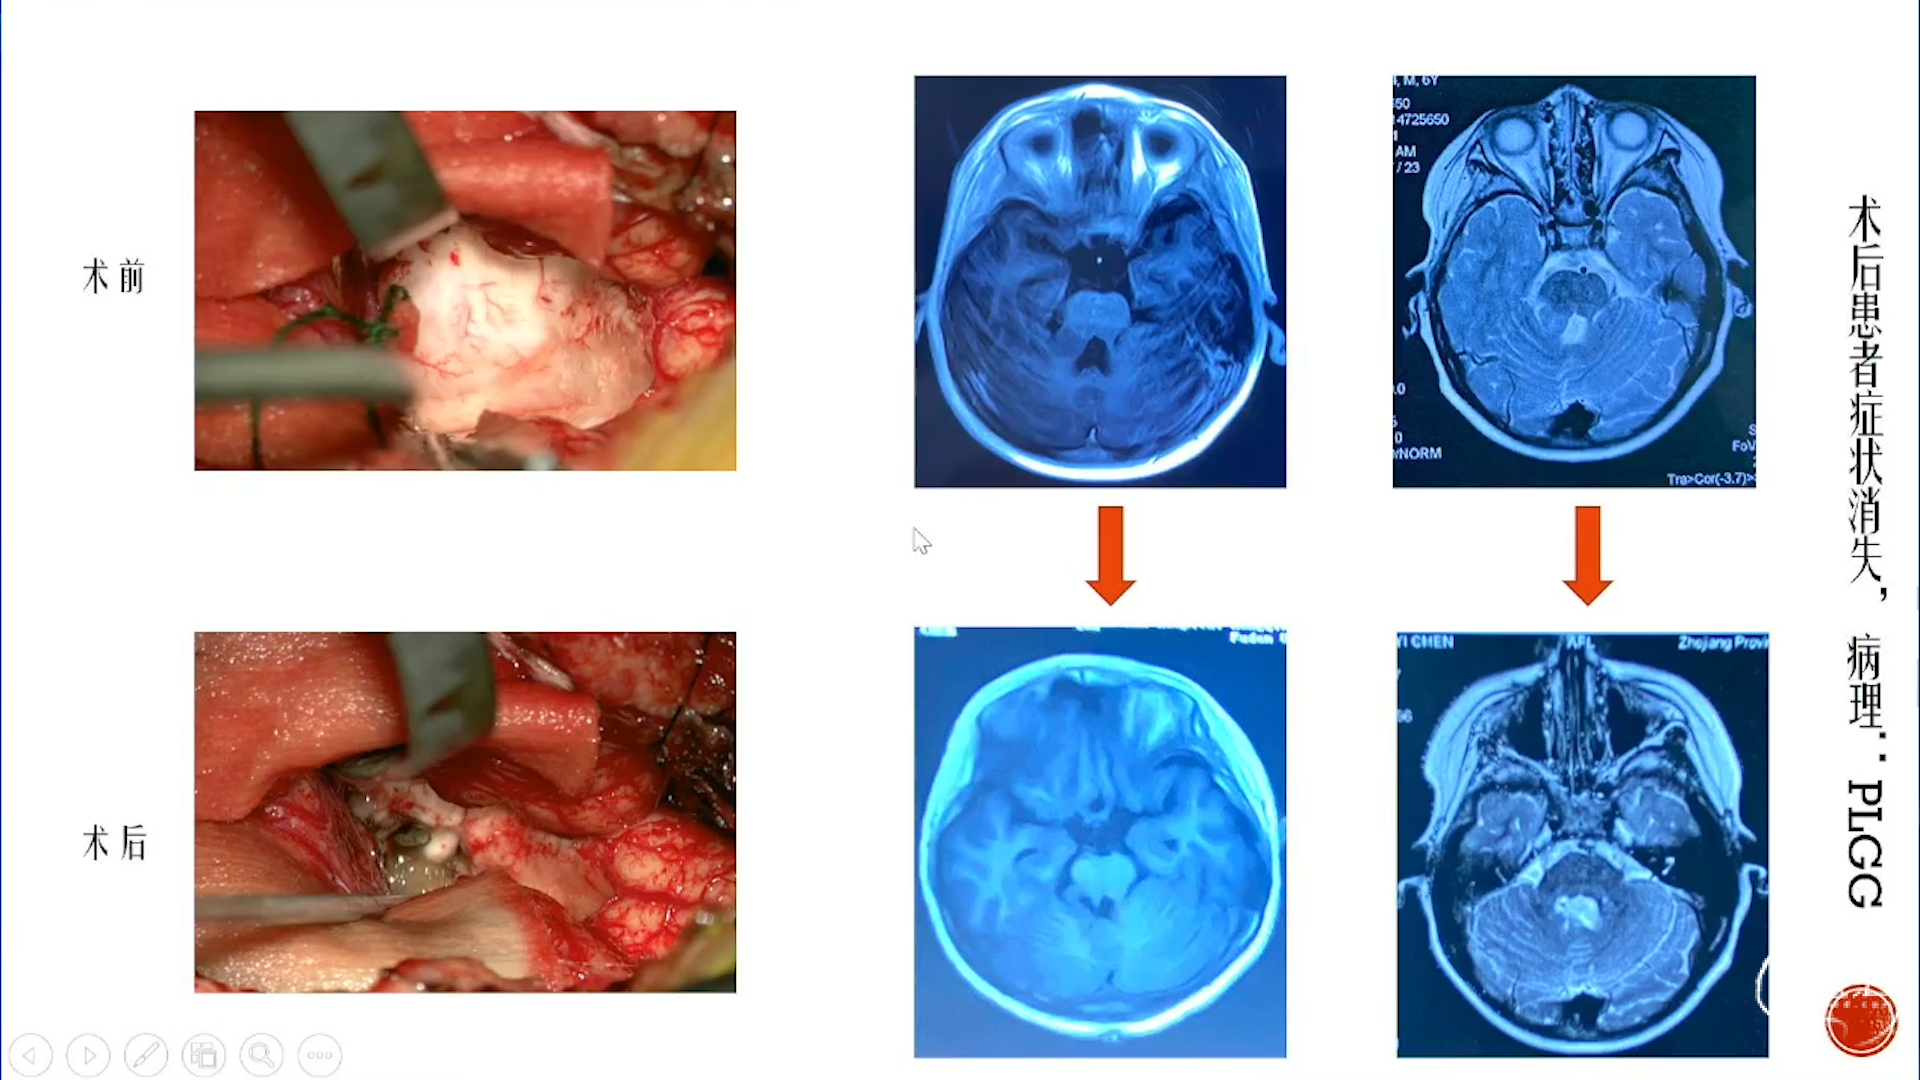

小脑星形细胞肿瘤

大脑半球儿童低级别胶质瘤